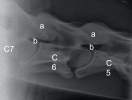

5. – 7. Halswirbel

Die Facettengelenke (a) sind massiv vergrössert und nach oben und unten unregelmässig zugebildet. Die Austrittslöcher (b) sind stark eingeengt.